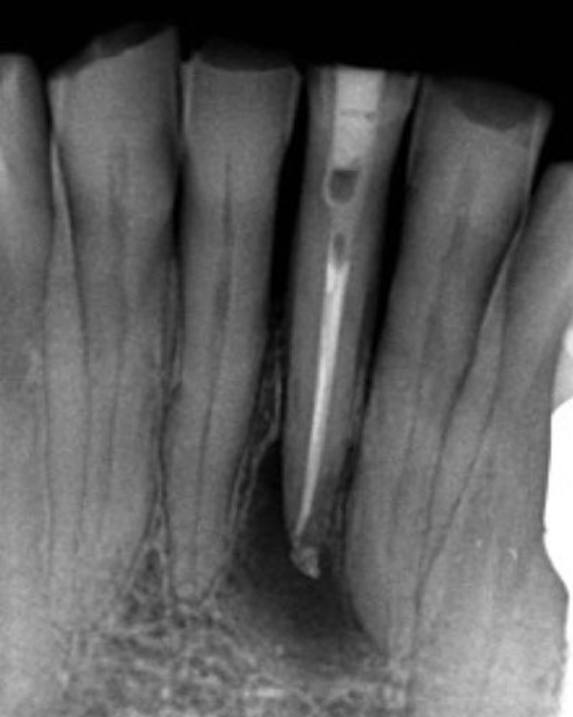

3. What Condition can be seen in this X ray regarding the tooth # 2.2?